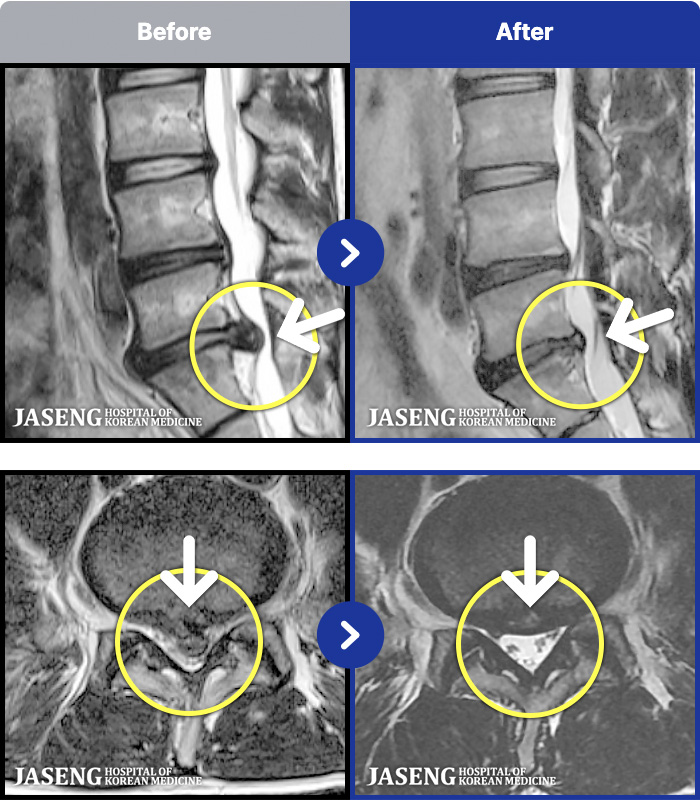

1,286 MRI ũ ʸ Ȯϼ.